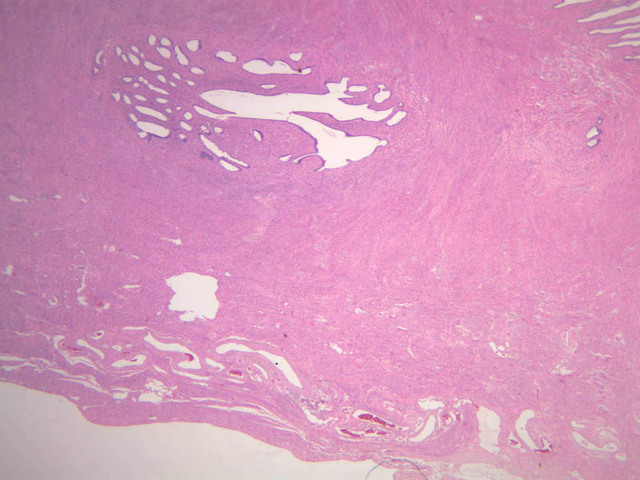

The uterus is a pear-shaped muscular organ, somewhat flattened from front to back. The expanded upper portion is referred to as the fundus, while its lower part, which protrudes into the vagina, is called the cervix. The lumen of the uterus is slit-like and is in communication with that of the uterine tubes (B-97, monkey uterus [1x, 1x, 1x, 1x]). The wall of the uterus consists of three layers: perimetrium, myometrium, and endometrium (B-97 [1x, 1x-labeled] [1x, 1x, 1x]; B-100 [1x, 1x]). The perimetrium is peritoneum which covers the uterus, but is lacking in the posterocaudal third below the peritoneal reflection (B-97 [2.5x, 10x, 20x, 40x]). The myometrium is the very thick middle layer consisting of bundles of smooth muscle cells arranged into several interwoven layers (slide B-93 [1x-labeled, 2.5x] [1x, 2.5x] [1x, 2.5x] [2.5x, 10x, 20x, 40x]). The endometrium is the innermost layer and is a glandular mucosa (B-97 [2.5x, 10x, 20x] [2.5x, 10x, 20x] [2.5x, 10x, 20x, 40x]). It consists of a surface epithelium which is invaginated into tubes called uterine glands. The glands penetrate into a very thick lamina propria referred to as the endometrial stroma. The surface epithelium is a mixture of ciliated and non-ciliated simple columnar cells, whereas the glandular epithelium consists mainly of non-ciliated secretory cells. The endometrial stroma has the appearance of a loose, rather cellular mesenchyme with numerous blood vessels.

The endometrium is subdivided into two main parts; the basalis and the functionalis (slide B-97). The basalis is deep, lying adjacent to the myometrium, it consists of stroma and the closed ends of the uterine glands and is not sloughed during menstruation. The functionalis is upper zone consisting of the remainder of the uterine glands with intervening stroma. It is lost during menstruation, but is replaced again with each menstrual cycle, by proliferation of the persisting elements in the basalis.

The menstrual cycle is a continuous series of events, dominated by the endocrine activity of the ovary, which repeats itself with a 28 day period. The endometrium participates by undergoing a series of structural changes which are roughly divided into three categories, the proliferative, secretory, and menstrual phases. These phases are listed below, examine each of the uterine slides and determine to which phase it belongs.

The menstrual phase lasts 1 -5 days, and corresponds to ovarian menstrual phase; i.e., degeneration of corpus luteum with consequent decrease in estrogen and progesterone levels. During this phase the functionalis sloughs off leaving the basalis. Just prior to sloughing, the glands are extremely dilated and tortuous.

Proliferative Phase

This phase occurs during days 7 to 14 and corresponds to the ovarian follicular phase with rising levels of estrogens. The functionalis layer is replaced by growth of the endometrial elements in the basalis. The glands are usually straight tubes extending from the surface. Epithelial cells become taller and accumulate glycogen basal to their nuclei. (slide B-93 [2.5x, 10x, 20x, 40x]; B-97 [2.5x, 10x, 20x, 40x])